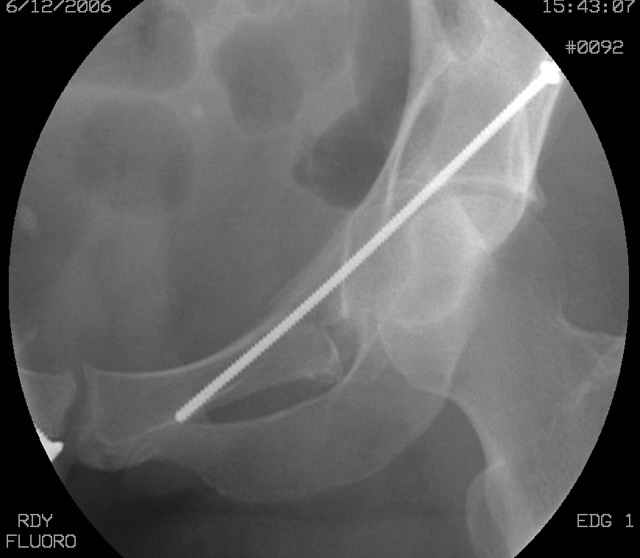

Prone Inlet

OK, now we're inserting the drill percutaneosuy using a sleeve. This fluoro shot is not for this patient (notice no clamp) but I was too lazy to go searching the PACS for one with the clamp on, so pretend...I'll save the next ones and send along...the imaging is the same and the clamp doesn't obstruct imaging other than very rarely...you can always tilt the C-arm a bit to clear it if the clamp obstructs the exact spot that you'd like to see. We'll assume that everyone knows the safe zone for a medullary ramus screw. Use a calibrated drill and sleeve of known length to simplify your life...or use Alex's fancy cannulated screws...I like 3.5mm screws because the oscillating 2.5mm drill bounces and remains intraosseus when it oscillates and contacts endosteal cortical ramus... so will the screw, and like a long bent screw IF the fracture is clamped... if unclamped, when the screw contacts the endosteum, it pushes the reduction apart instead of bouncing. The big 7mm cannulated screws fit few patients and extrude...we very rarely use them any more...you'll see an old one later.

Prone Obturator-Outlet

Screw insertion using the obturator-outlet combination image.